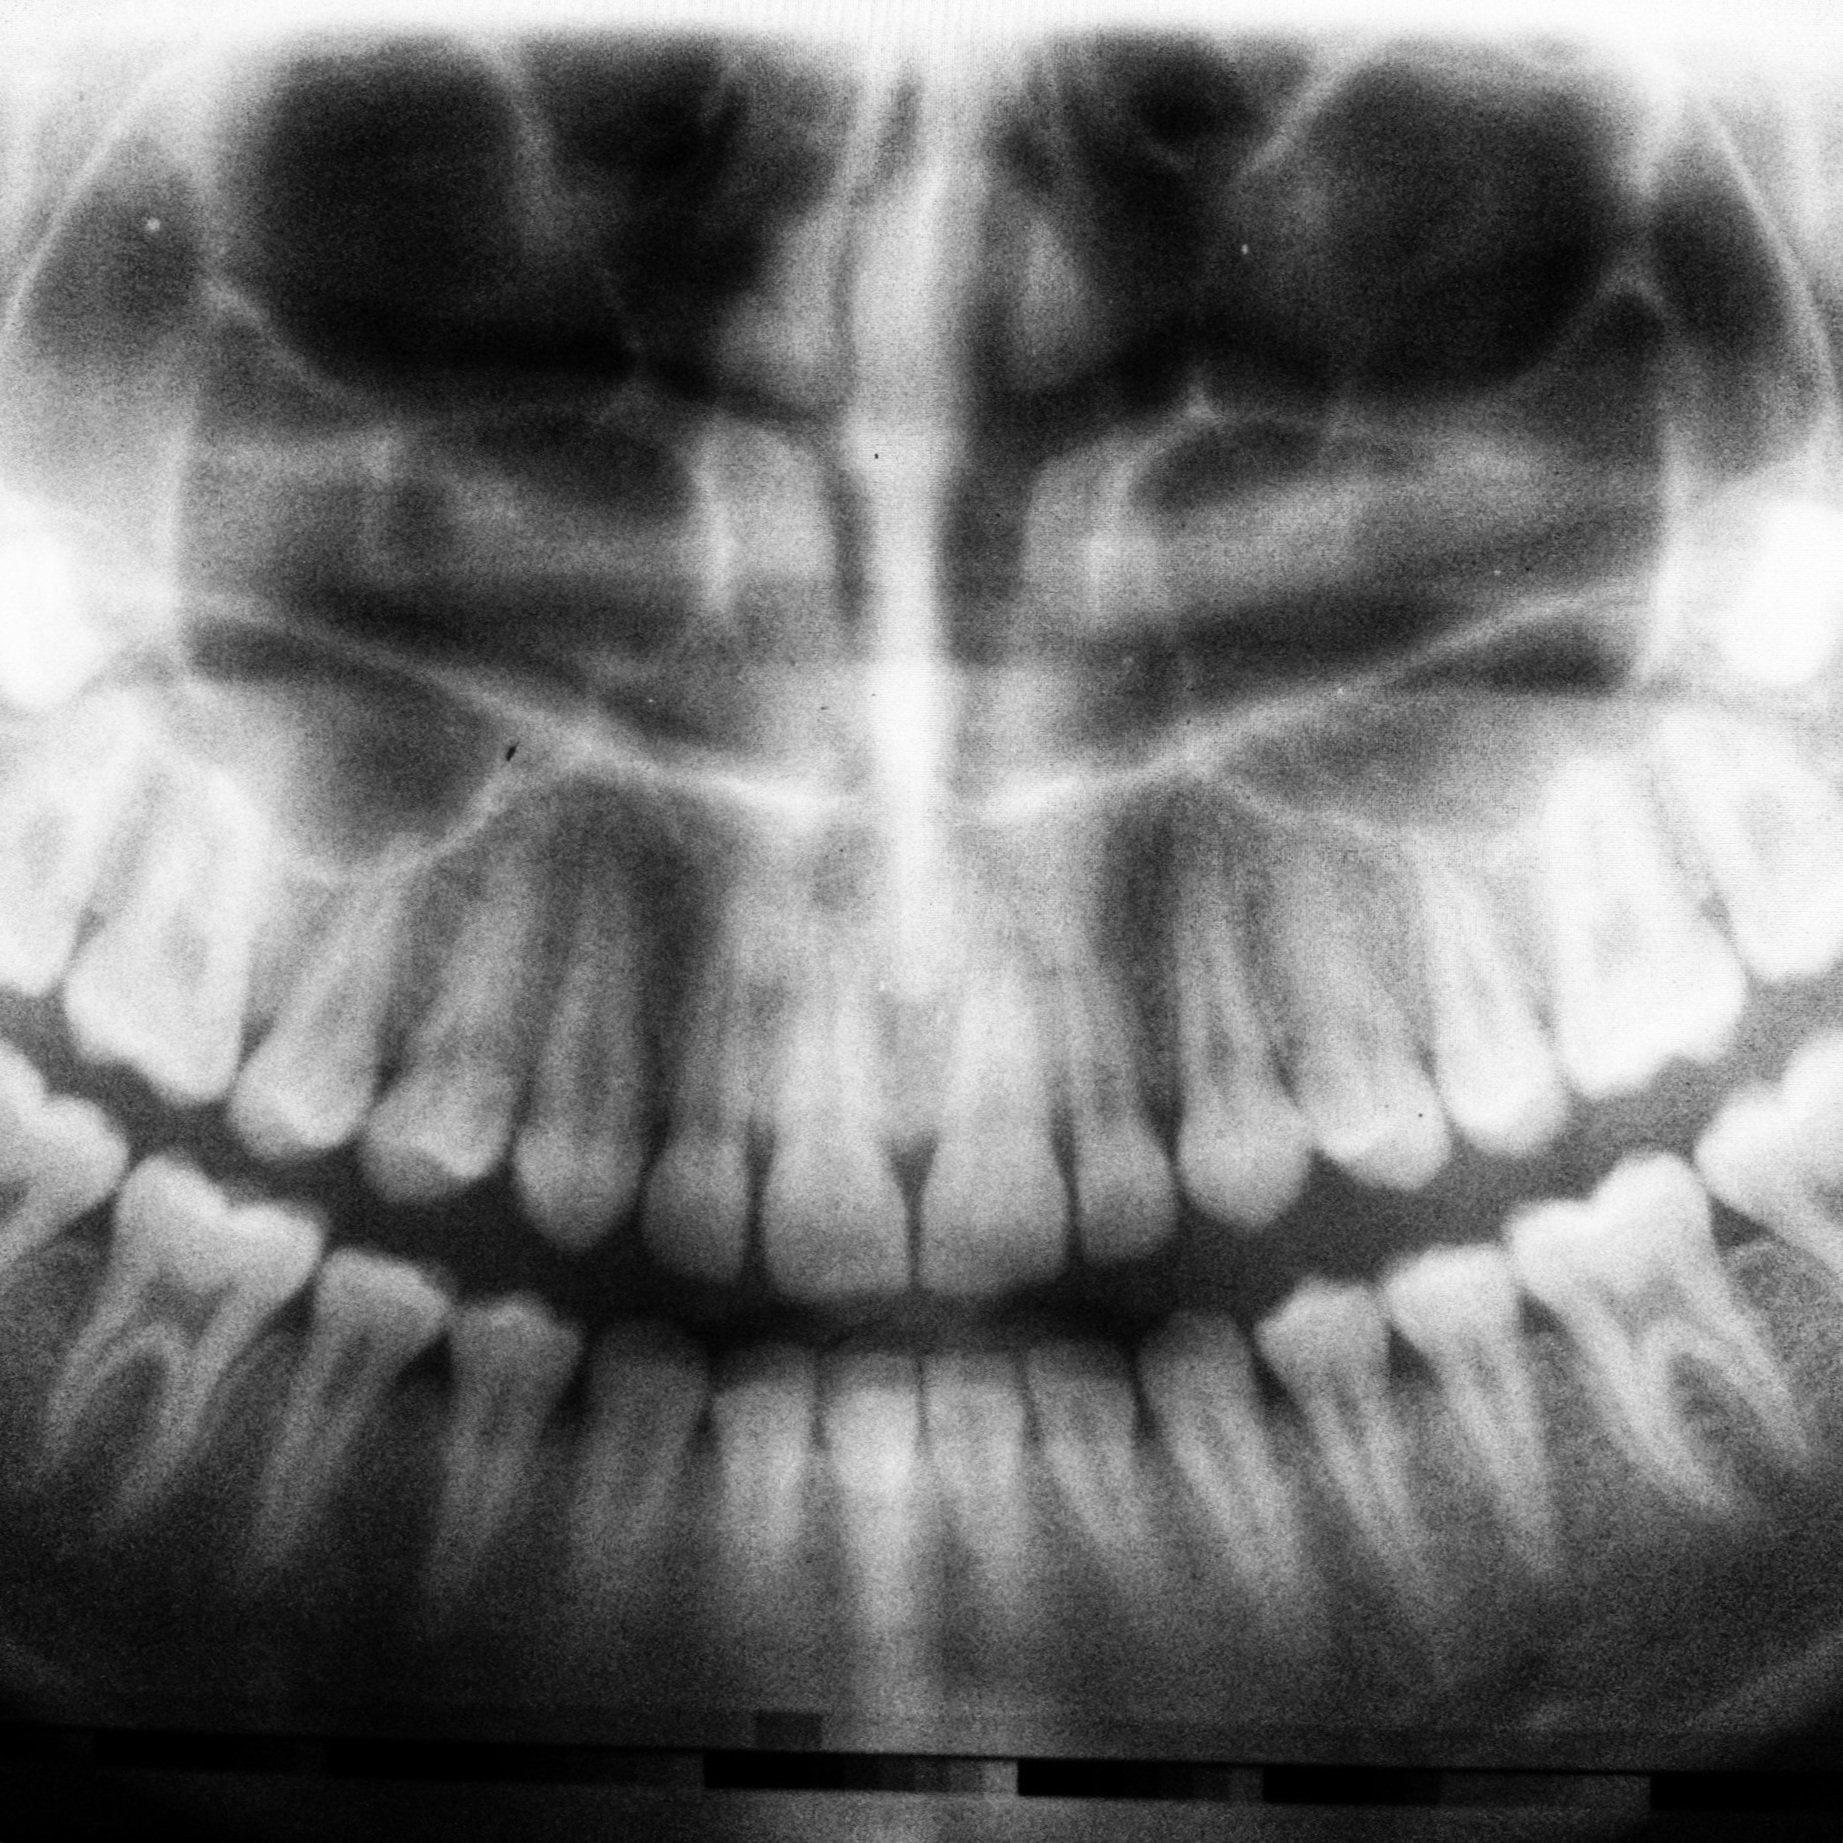

Digitale Röntgenbilder

Digitale Röntgenbilder sind eine moderne diagnostische Methode, die präzise und hochauflösende Bilder der Zähne und des Kieferbereichs liefert. Sie reduzieren die Strahlenbelastung und tragen zu einer effizienten Behandlung bei.